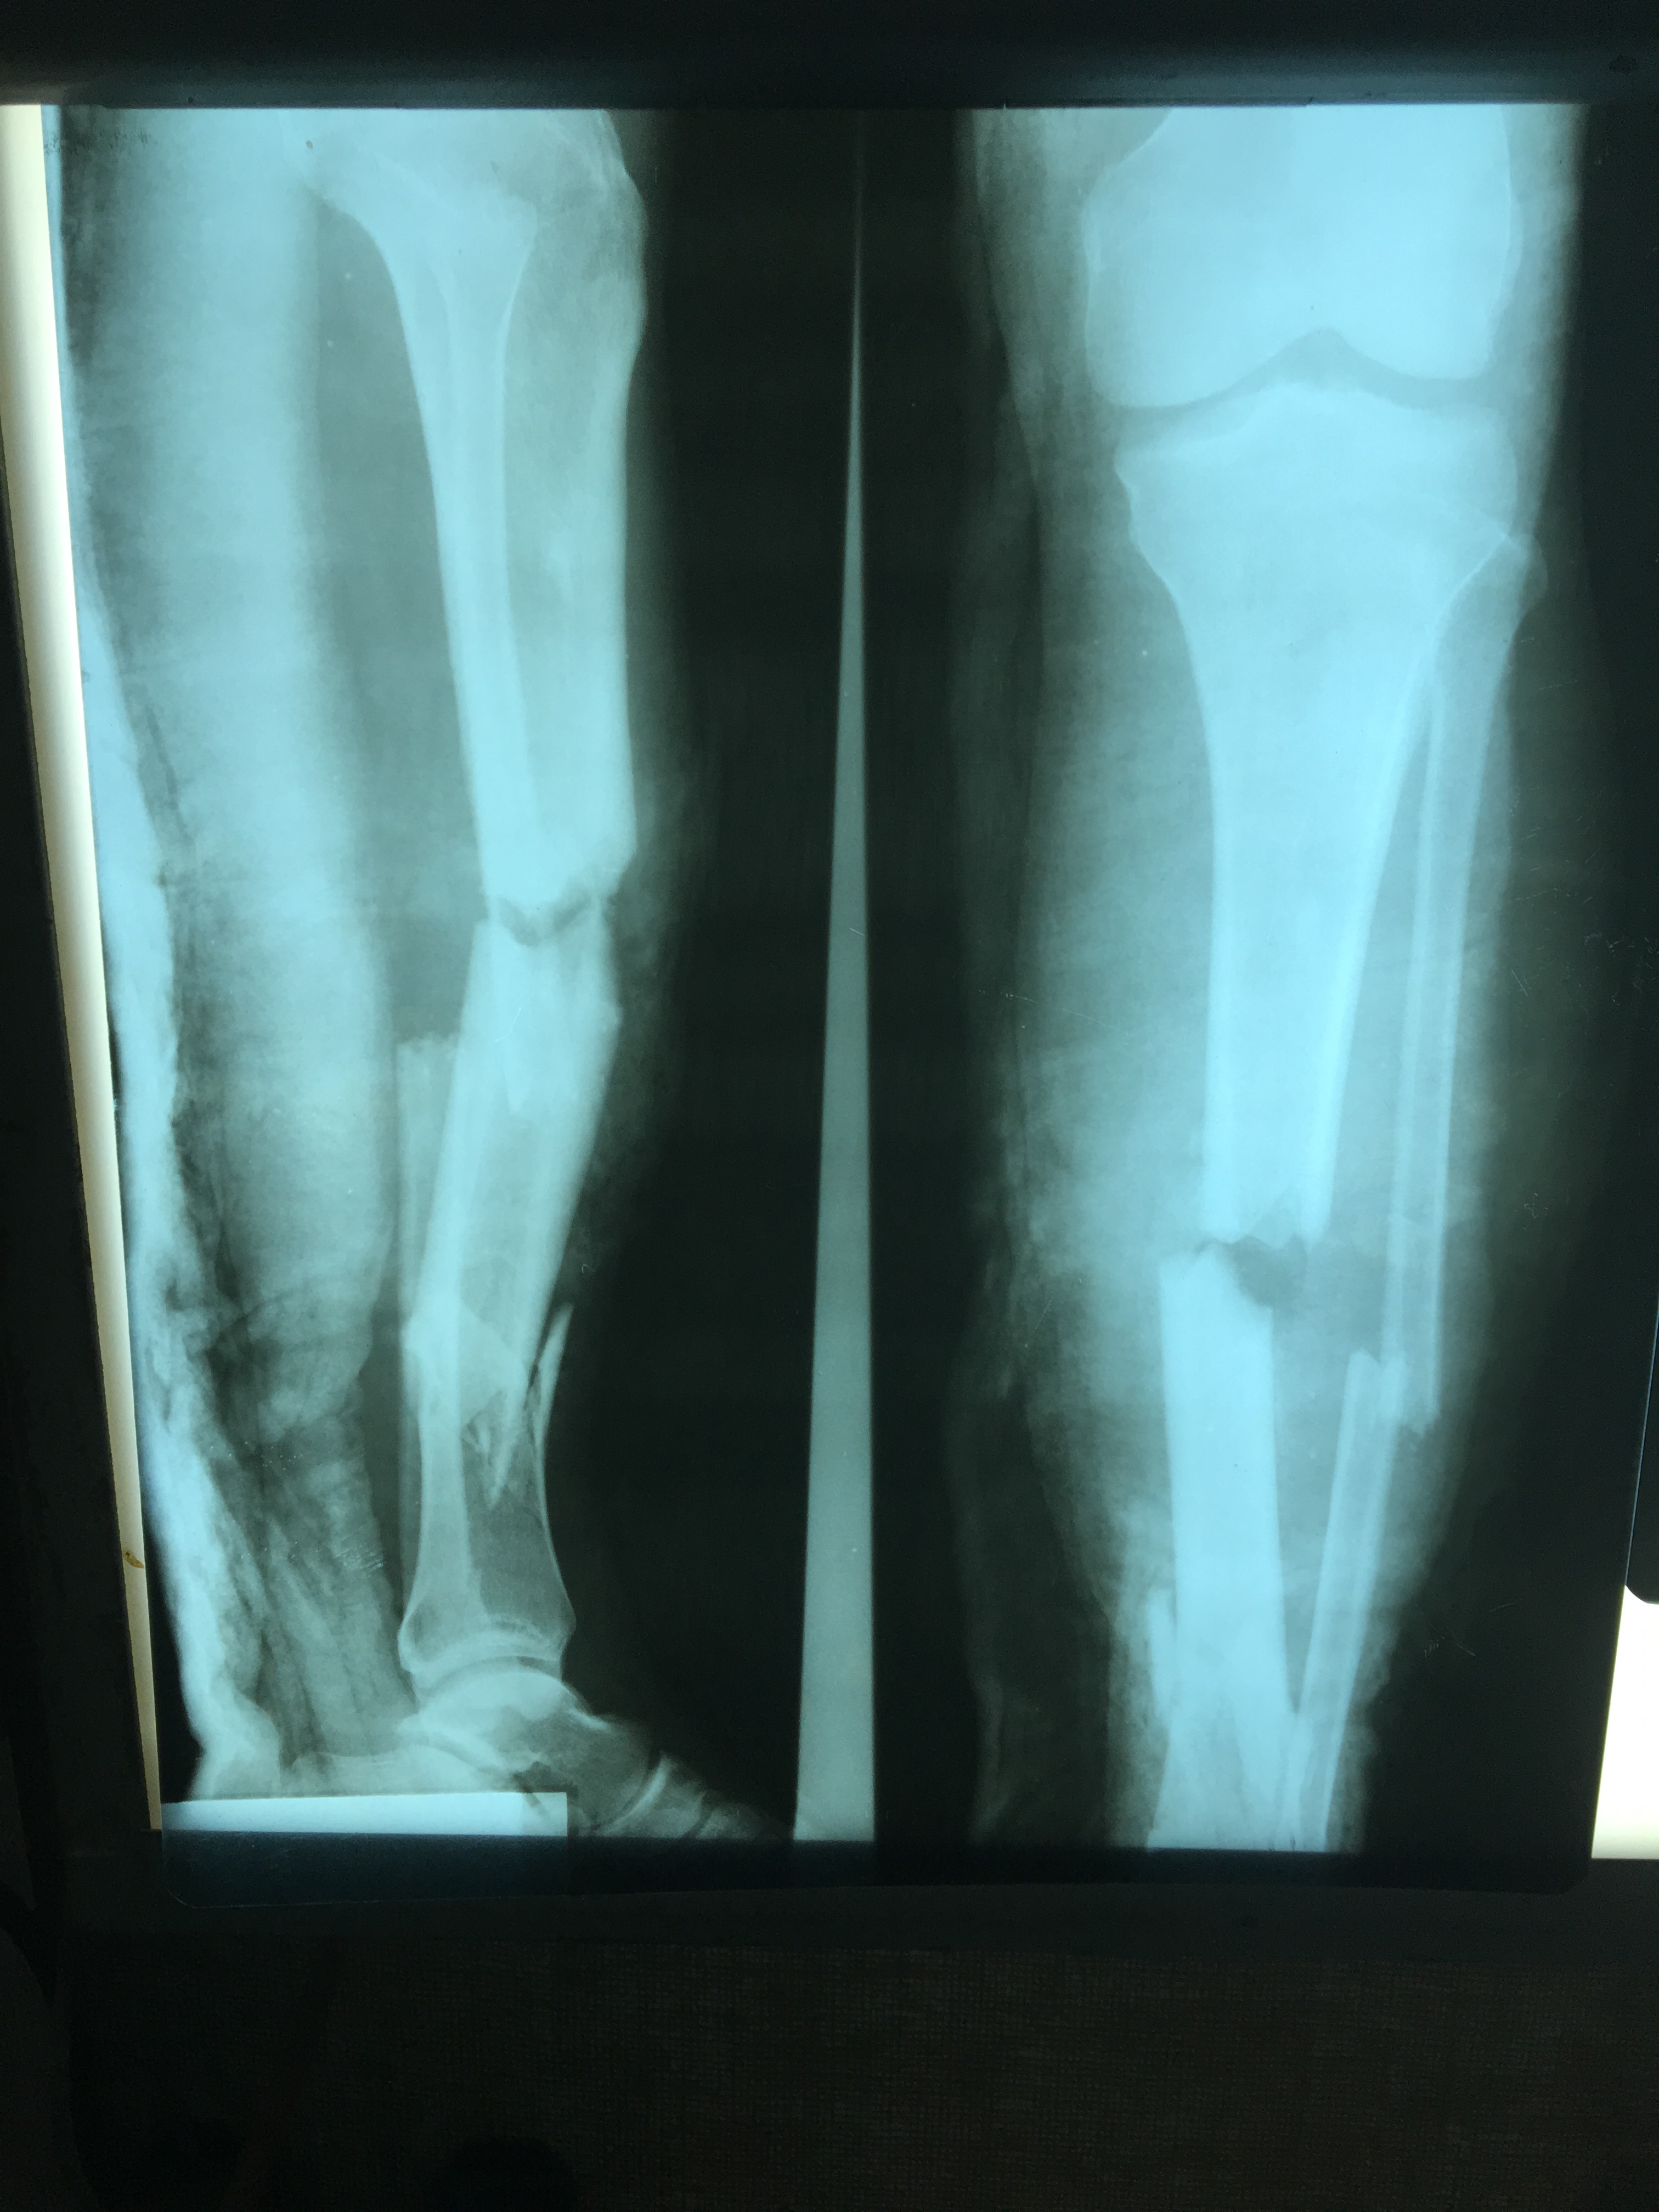

Donny V